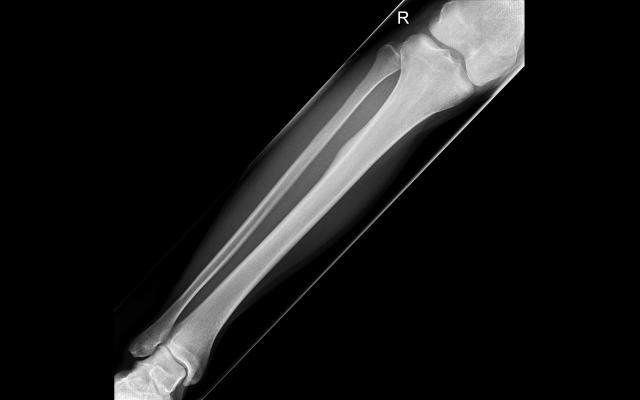

Dit artikel is alleen beschikbaar als PDF.Lees de PDF Artikelinformatie 11 februari 1878 Citeer dit artikel als Ned Tijdschr Geneeskd. 1878;22:645-7 Heb je nog vragen na het lezen van dit artikel? Check onze AI-tool en verbaas je over de antwoorden. ASK NTVG Ook interessant Diagnose in beeld Een jonge man met nachtelijke pijn in een scheenbeen Beeldquiz Een jonge man met nachtelijke pijn in een scheenbeen Nieuws Individueele en regionaire geuren van den mensch Meer gerelateerd … Reacties Login om een reactie te plaatsen